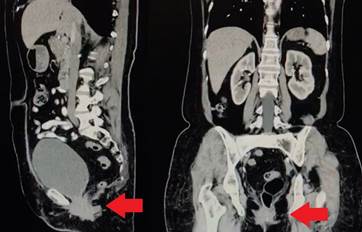

Se trata de una paciente femenina de 64 años, con antecedente de histerectomía por abordaje abdominal 35 años atrás y sin otros antecedentes de importancia. Consultó por presentar sensación de masa en la vagina. Inicialmente fue valorada por el servicio de ginecología, quienes encontraron un prolapso vaginal y abultamiento del labio mayor izquierdo. Ante estos hallazgos, se realizó una tomografía computarizada contrastada de abdomen donde se encontraron alteraciones compatibles con una hernia perineal (Figura 1).

Figura 1. Tomografía computarizada en la que se observa la hernia señalada por la flecha roja en los cortes sagital y coronal.